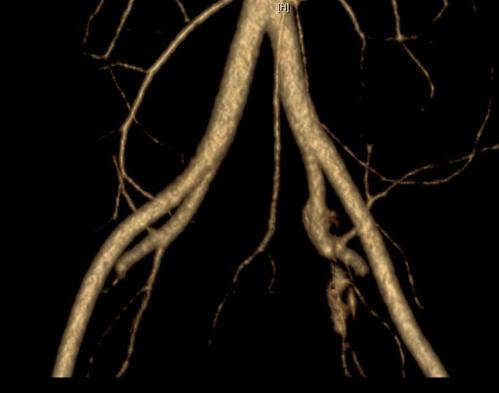

三个病例经过腹盆腔增强CT发现左侧髂总静脉受压闭塞。

箭头所示为几乎消失的左侧髂总静脉